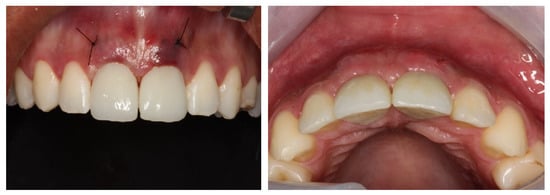

Result and Follow-Up